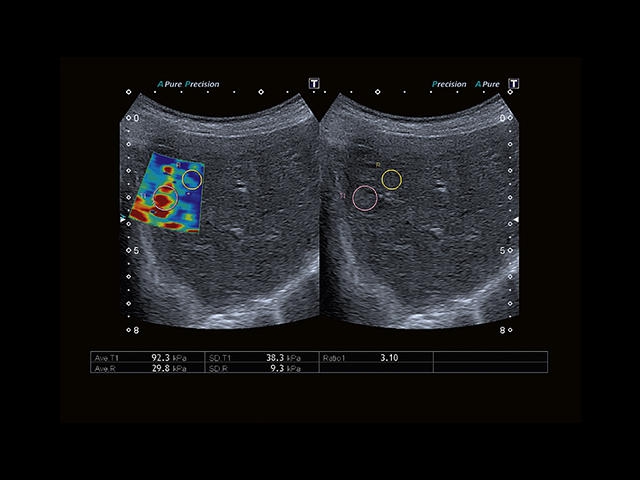

Обновленная версия легендарного УЗ-сканера. Стационарный аппарат экспертного класса Aplio 500 Toshiba NEW, визуализирует анатомические структуры в высоком разрешении. Модель позволяет выявить микрокальцификаты, новообразования, нарушения в работе сердца, сосудов и мышц. Присутствует функция виртуальной эндоскопии, 4D-сканирования, эластометрии тканей, УЗИ с контрастированием. За повышение качества изображения отвечают технологии ApliPure и Superb Microvascular Imaging. Первая задействует возможности пространственного и частотного кодирования, формирует цельный визуальный ряд с сохранением клинических маркеров. Вторая улучшает отображение микрососудистого русла, используя доплеровский эффект. Модель оснащена 21-дюймовым монитором, имеет 4 активных порта. Возможно подключение педиатрических, интраоперационных, лапароскопических и чреспищеводных датчиков.

• SMI. Опция, упрощающая визуализацию микроциркуляторного русла. С ее помощью обследуются сосуды с низкой интенсивностью кровотока, изучаются наиболее тонкие структуры. SMI упрощает диагностику новообразований, минимизирует вероятность ошибки.